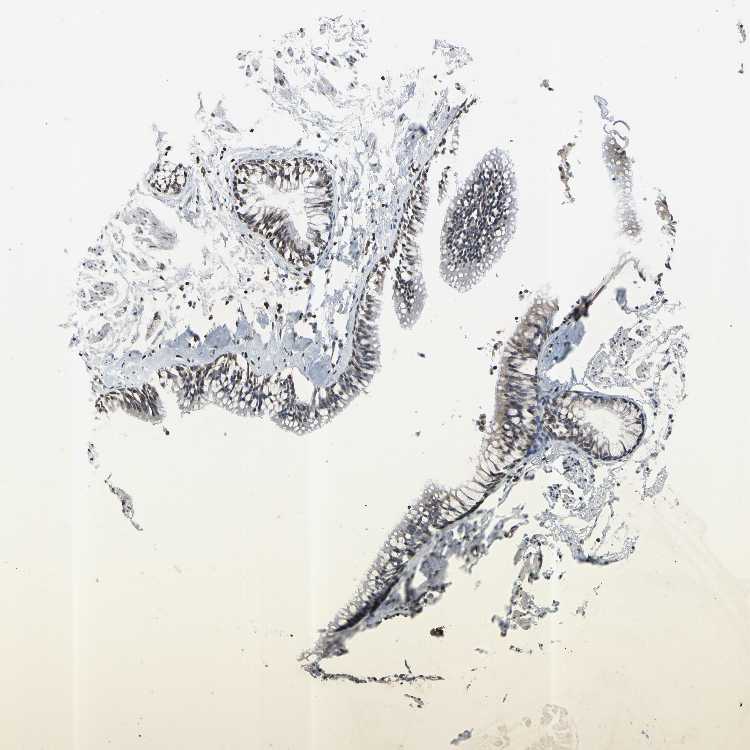

ADIPOSE TISSUE - Antibody stainingi

Antibody staining in the annotated cell types in the current human tissue is reported as not detected, low, medium, or high, based on conventional immunohistochemistry profiling in selected tissues. This score is based on the combination of the staining intensity and fraction of stained cells.

Each image is clickable and will lead to virtual microscopy that enables deeper exploration of all samples and also displays staining intensity scores, fraction scores and subcellular localization as well as patient and tissue information for each sample.

Antibody HPA003595Antibody HPA024006Antibody CAB009434Antibody CAB056159Antibody CAB080011

Adipocytes Not detectedNot detectedLowNot detectedNot detected